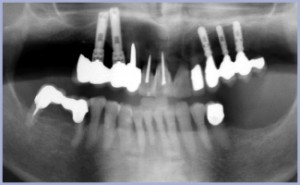

Si stabilisce un piano di trattamento che preveda una riabilitazione del 2° quadrante mediante protesi fissa supportata da impianti, secondo una procedura a due tempi (impianti post-estrattivi immediati e carico a distanza ad avvenuta osteointegrazione). L’intervento è trattato in ansiolisi. Si inseriscono 2 impianti diametro 4,1 mm lunghezza 12 mm post-estrattivi immediati in sede +3 e +5. Si inserisce un impianto diametro 3,3 mm lunghezza 12 mm su sito maturo in sede +4. In sede +3 si esegue un’espansione verticale di cresta secondo tecnica OSFE – Osteotomy Sinus Floor Elevation – di Summers per poter utilizzare un impianto sufficientemente lungo. Si esegue un intervento rigenerativo nella zona crestale in presenza di deiscenza alveolare, tramite apposizione di bone chips. Analogo trattamento si esegue in sede +5 (OSFE + bone chips). In sede +4 si esegue un’espansione trasversale tramite tecnica REO – Ridge Expansion Osteotomy – (figg. 5-10). All’atto dell’intervento implantare si confeziona, per fini estetici, un provvisorio di resina +2+6 (fig. 11) da mantenere per tutto il periodo della guarigione conservando il pilastro naturale +6, già rizectomizzato (fig. 12). Ad osteointegrazione avvenuta si effettua il secondo rientro chirurgico che permette di rimuovere i tappi di chiusura e di inserire i tappi di guarigione (fig. 13). Il pilastro +6, già rizectomizzato e non più recuperabile, viene estratto al momento della finalizzazione protesica (figg. 14-19).

- Fig. 2